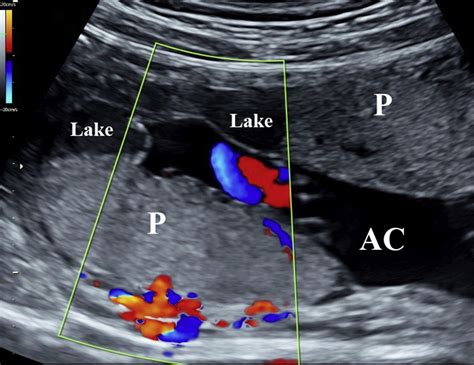

The placenta is a temporary organ that develops in the uterus during pregnancy. It serves as a lifeline between the mother and the fetus, facilitating the exchange of nutrients, gases, and waste products. Lakes In The Placenta refer to small, fluid-filled spaces within the placental tissue. These lakes are not typically visible to the naked eye but can be detected through advanced imaging techniques and histological examinations.

• Ultrasound Imaging: High-resolution ultrasound can sometimes detect the presence of lakes, although this method is not always reliable.

• Magnetic Resonance Imaging (MRI): MRI provides detailed images of the placenta and can help identify lakes more accurately.

• placental lake on ultrasound